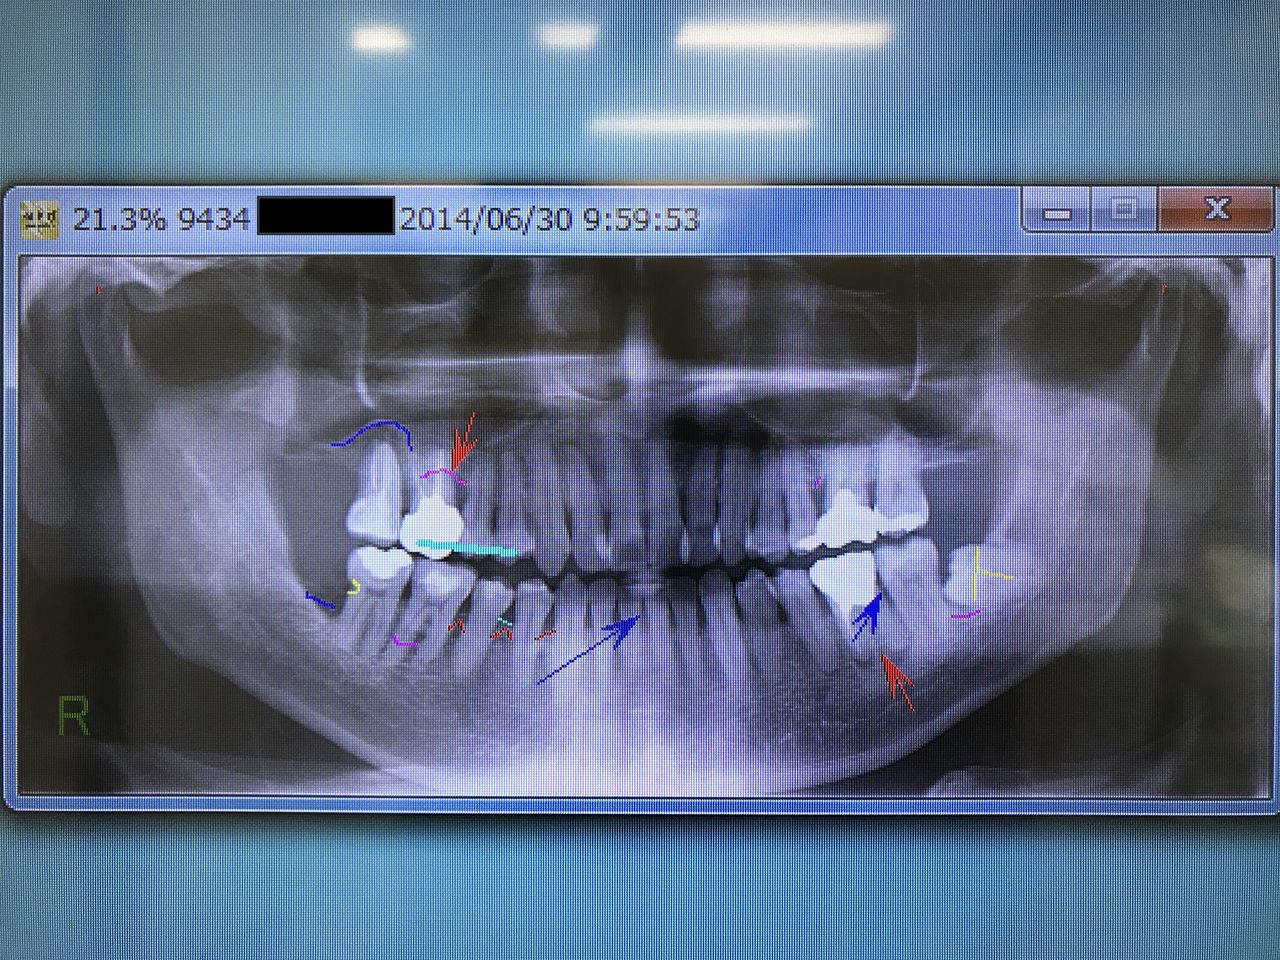

『半年前から右上奥歯が浮いた感じがする。』という主訴で来院された患者さん。口腔内所見の特筆すべき点として、噛み合せが Scissors bite(鋏状咬合)であることが挙げられます。

エックス線検査をすると歯周病があり、長年にわたり部分的な治療に終始していて、虫歯の治療を数年おきに、また歯石除去も治療のついでに受けてきたとのこと。